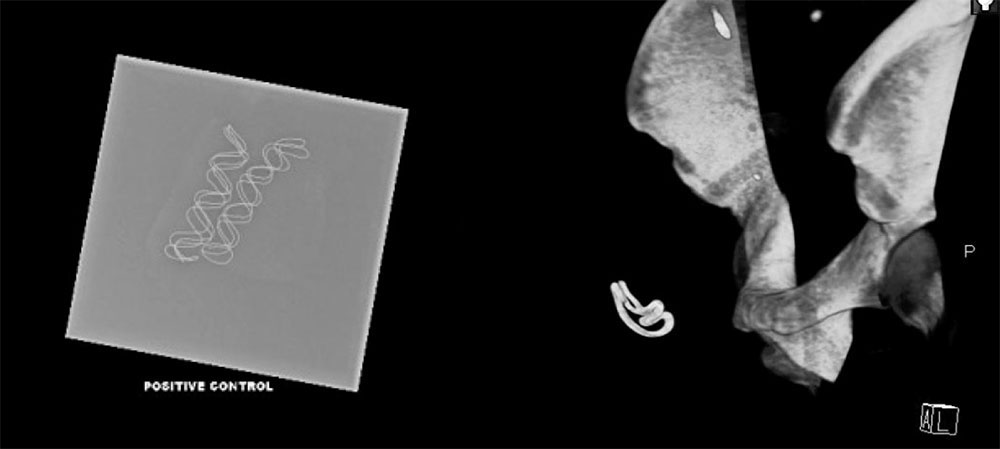

Intraoperative Radiography

|

Intraoperative Radiography

|

Intraoperative Radiography

|

Intraoperative Radiography

|

Intraoperative Radiography  |

Intraoperative Radiography  |